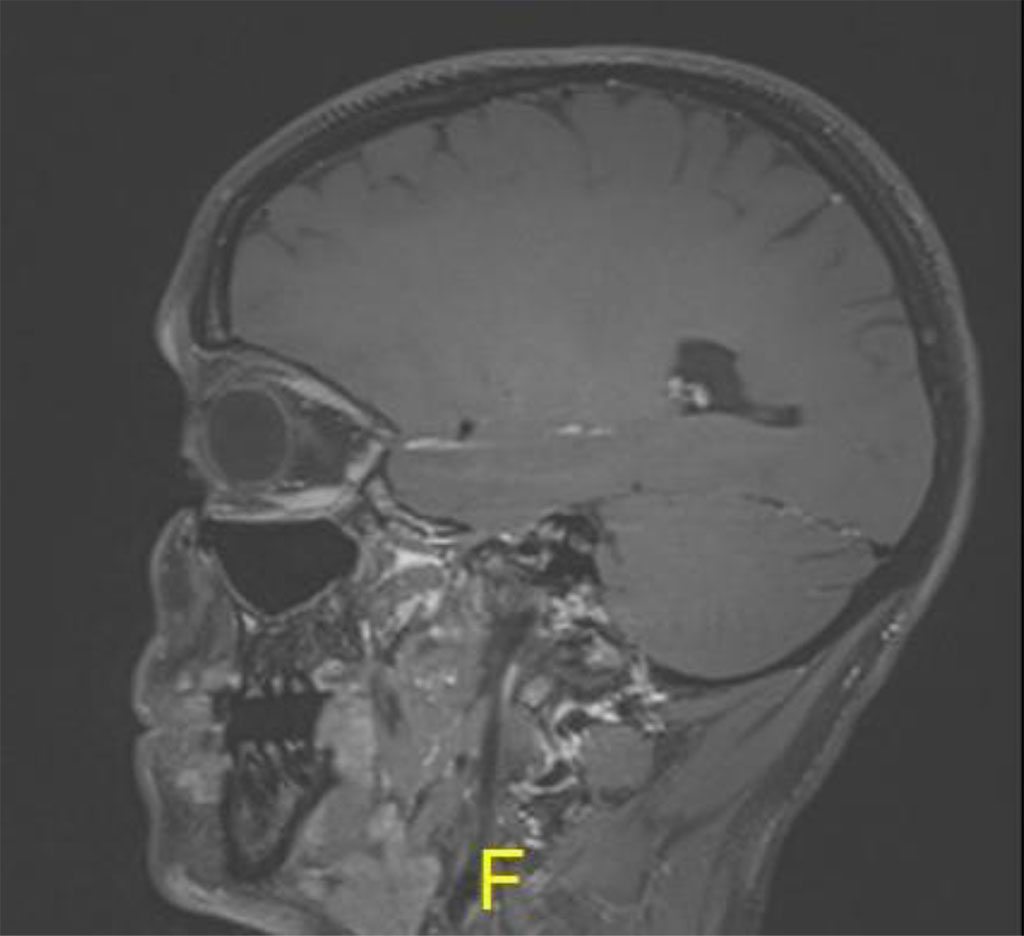

Her symptoms began and increased during her second pregnancy. She was not pregnant at the time of presentation. Magnetic resonance imaging (MRI) with Gadolinium and fat suppression revealed a large vascular lesion in the left orbit (Figures 2a,b).

Figure 2b: Sagital MR T1 demonstrating left inferior orbital lesion